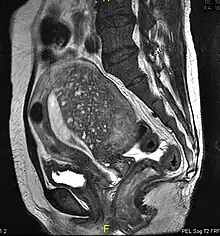

Sagittal MRI of a woman's pelvis showing a uterus with adenomyosis in the posterior wall. Gross enlargement of the posterior wall is noted, with many foci of hyperintensity.

Magnetic resonance imaging

Magnetic resonance imaging (MRI) provides slightly better diagnostic capability compared to TVUS, due to the increased ability of MRI to differentiate objectively between different types of soft tissue.[24] This is possible with MRI's higher spatial and contrast resolution. Overall, it is estimated that MRI has a sensitivity of 74% and specificity of 91% for the detection of adenomyosis.[11] Diagnosis through MRI focuses predominately upon investigating the junctional zone. The uterus will have a thickened junctional zone with darker/diminished signal on both T1 and T2 weighted sequences.[24]

Three objective measures of the junctional zone can be used to diagnose adenomyosis.[24]

1. A thickness of the junctional zone greater than 8–12 mm. Less than 8 mm is normal.

2. A junctional zone width being greater than 40% of the width of the myometrium.

3. Variability in the width of the junctional zone being greater than 5 mm.

Interspersed within the thickened, darker signal of the junctional zone, one will often see foci of hyperintensity (bright spots) on the T2 weighted scans representing small cystically dilatated glands or more acute sites of microhemorrhage.[24]